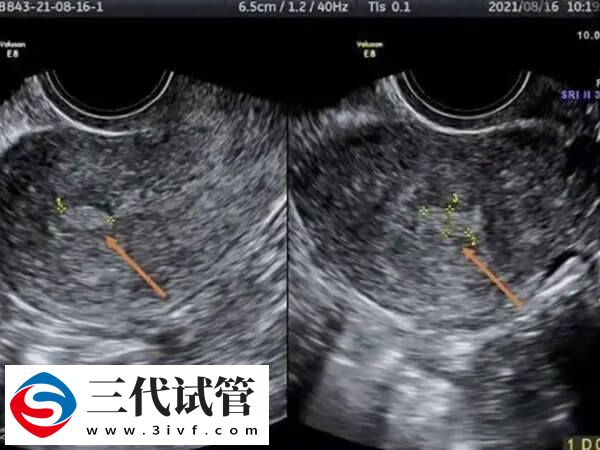

子宫内膜回声不均匀是超声检查对子宫内膜的一种描述,通常提示子宫内膜不规则增生导致的内膜厚薄不均,还有极少数患者可能存在子宫内膜息肉、子宫内膜不典型增生、子宫内膜癌等情况。这些情况就会影响试管移植的成功率,子宫内膜不均匀影不影响移植,情况有以下这些:

- 3. 子宫内膜回声不均匀是不正常的情况,可能属于功能性的改变,比如激素分泌水平紊乱所致的内膜不规则增生,也可能属于器质性病变,如结核性子宫内膜炎、子宫内膜息肉、子宫内膜癌等,此时需要做宫腔镜检查,内膜活检,明确诊断,不然对试管移植成功率会有较大影响。